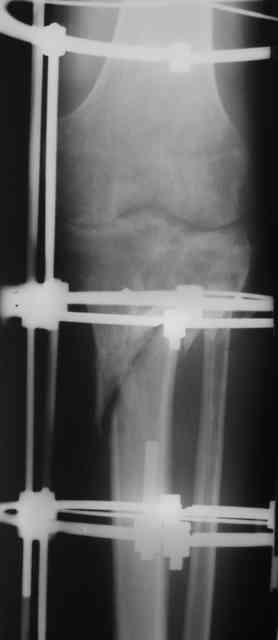

Р-граммы и фото за 4.05.2007 - 7-е сутки после операции.

Ход операции - линейным разрезом по передней поверхности голени обнажена зона ложного сустава большеберцовой кости. От кости отсепарованы медиально м/ткани. Из зоны ложного сустава убраны рубцовые ткани, мобилизован дистальный отломок. По передней поверхности удалены два осколка, связанных грануляциями. Произведено удаление грануляционной ткани из проксимального отломка (на вид сине-серого цвета), "чистого" гноя не было. Затем произведено наложение аппарата и репозиция отломков. По передне-медиальной поверхности образовался дефект до 4х2х2 см + полость в проксимальном отломке. Удаленные осколки очищены от грануляций, уложены в место дефекта, зажаты между отломками. После иссечения раны по передней поверхности, находящейся рядом с операционной раной, последняя ушита с большим натяжением.

Перелом мыщелка сросся. Проксимальный отломок очень порозный.

На перевязках - из раны небольшое кол-во сукровичного отделяемого. Отек голени умеренный, состояние кожи на фото.

Аппарат видел, репозиции не заметил. О "наложенном" аппарате: спицы в проксимальном отломке б\берцовой кости проведены очень низко, и опять только две, как и в первом аппарате. Почему только одна спица в дистальном парафрактурном кольце? Проксимальная база на бедре должна улучшить стабильность проксимального фрагмента tibia? Ничего подобного двумя спицами в одной базе при таком длинном рычаге вы не добьетесь, а вот совсем потерять движения в коленном суставе они почти гарантируют.

О репозиции: мыщелок сросся и слава Богу, но основные отломки фиксированы в вальгусном положении, собственно как и было, это критично. В чем состояла репозиция?